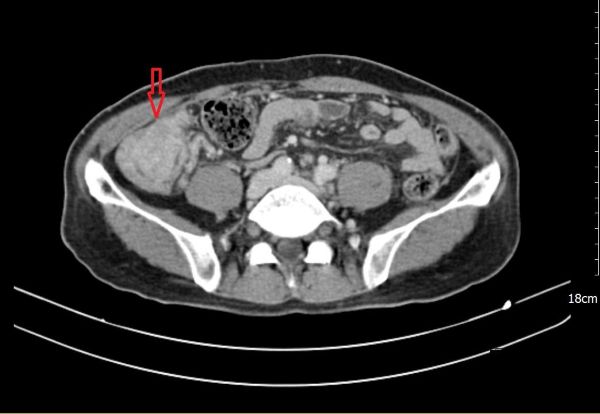

【記者吉雄世/高雄報導】66 歲的陳先生自去年八、九月起,陸續出現全身倦怠、食慾不振、腹脹與腹瀉等情形,短短兩個月內體重減少約6公斤,因身體不適至義大癌治療醫院一般外科趙頌慈醫師門診求診,經檢查後發現,血紅素偏低並合併營養狀況不佳,影像檢查發現罹患多發性結腸癌,且腫瘤已擴散至腹腔,對病人與家屬而言是噩耗。

在腫瘤反應與身體條件允許下,醫療團隊進一步評估後,建議接受「腹腔高壓氣霧化學治療(PIPAC)」。此為以腹腔鏡進行的微創治療方式,將化療藥物於高壓環境中霧化,使藥物能較均勻分佈於腹腔內,作為部分腹膜癌病人之治療選項之一。陳先生完成一個療程、共三次「腹腔高壓氣霧化學治療(PIPAC)」 後,臨床症狀與檢查結果顯示病情獲得控制,相關評估指標亦呈現改善趨勢。

後續在審慎評估風險與效益後,醫療團隊為陳先生安排腫瘤減積手術(CRS),並合併術中腹腔溫熱化學治療(HIPEC)。手術過程中,醫師清除腹腔內可見病竈,並以溫熱化療藥物進行腹腔循環灌注,期望降低殘留腫瘤負荷。術後恢復過程順利,並持續接受門診追蹤與治療照護。陳先生食慾、體力與日常活動能力逐步改善,生活品質也獲得提升。家屬表示,感謝醫療團隊在治療過程中提供清楚說明與完整照護,讓全家能安心面對治療歷程。